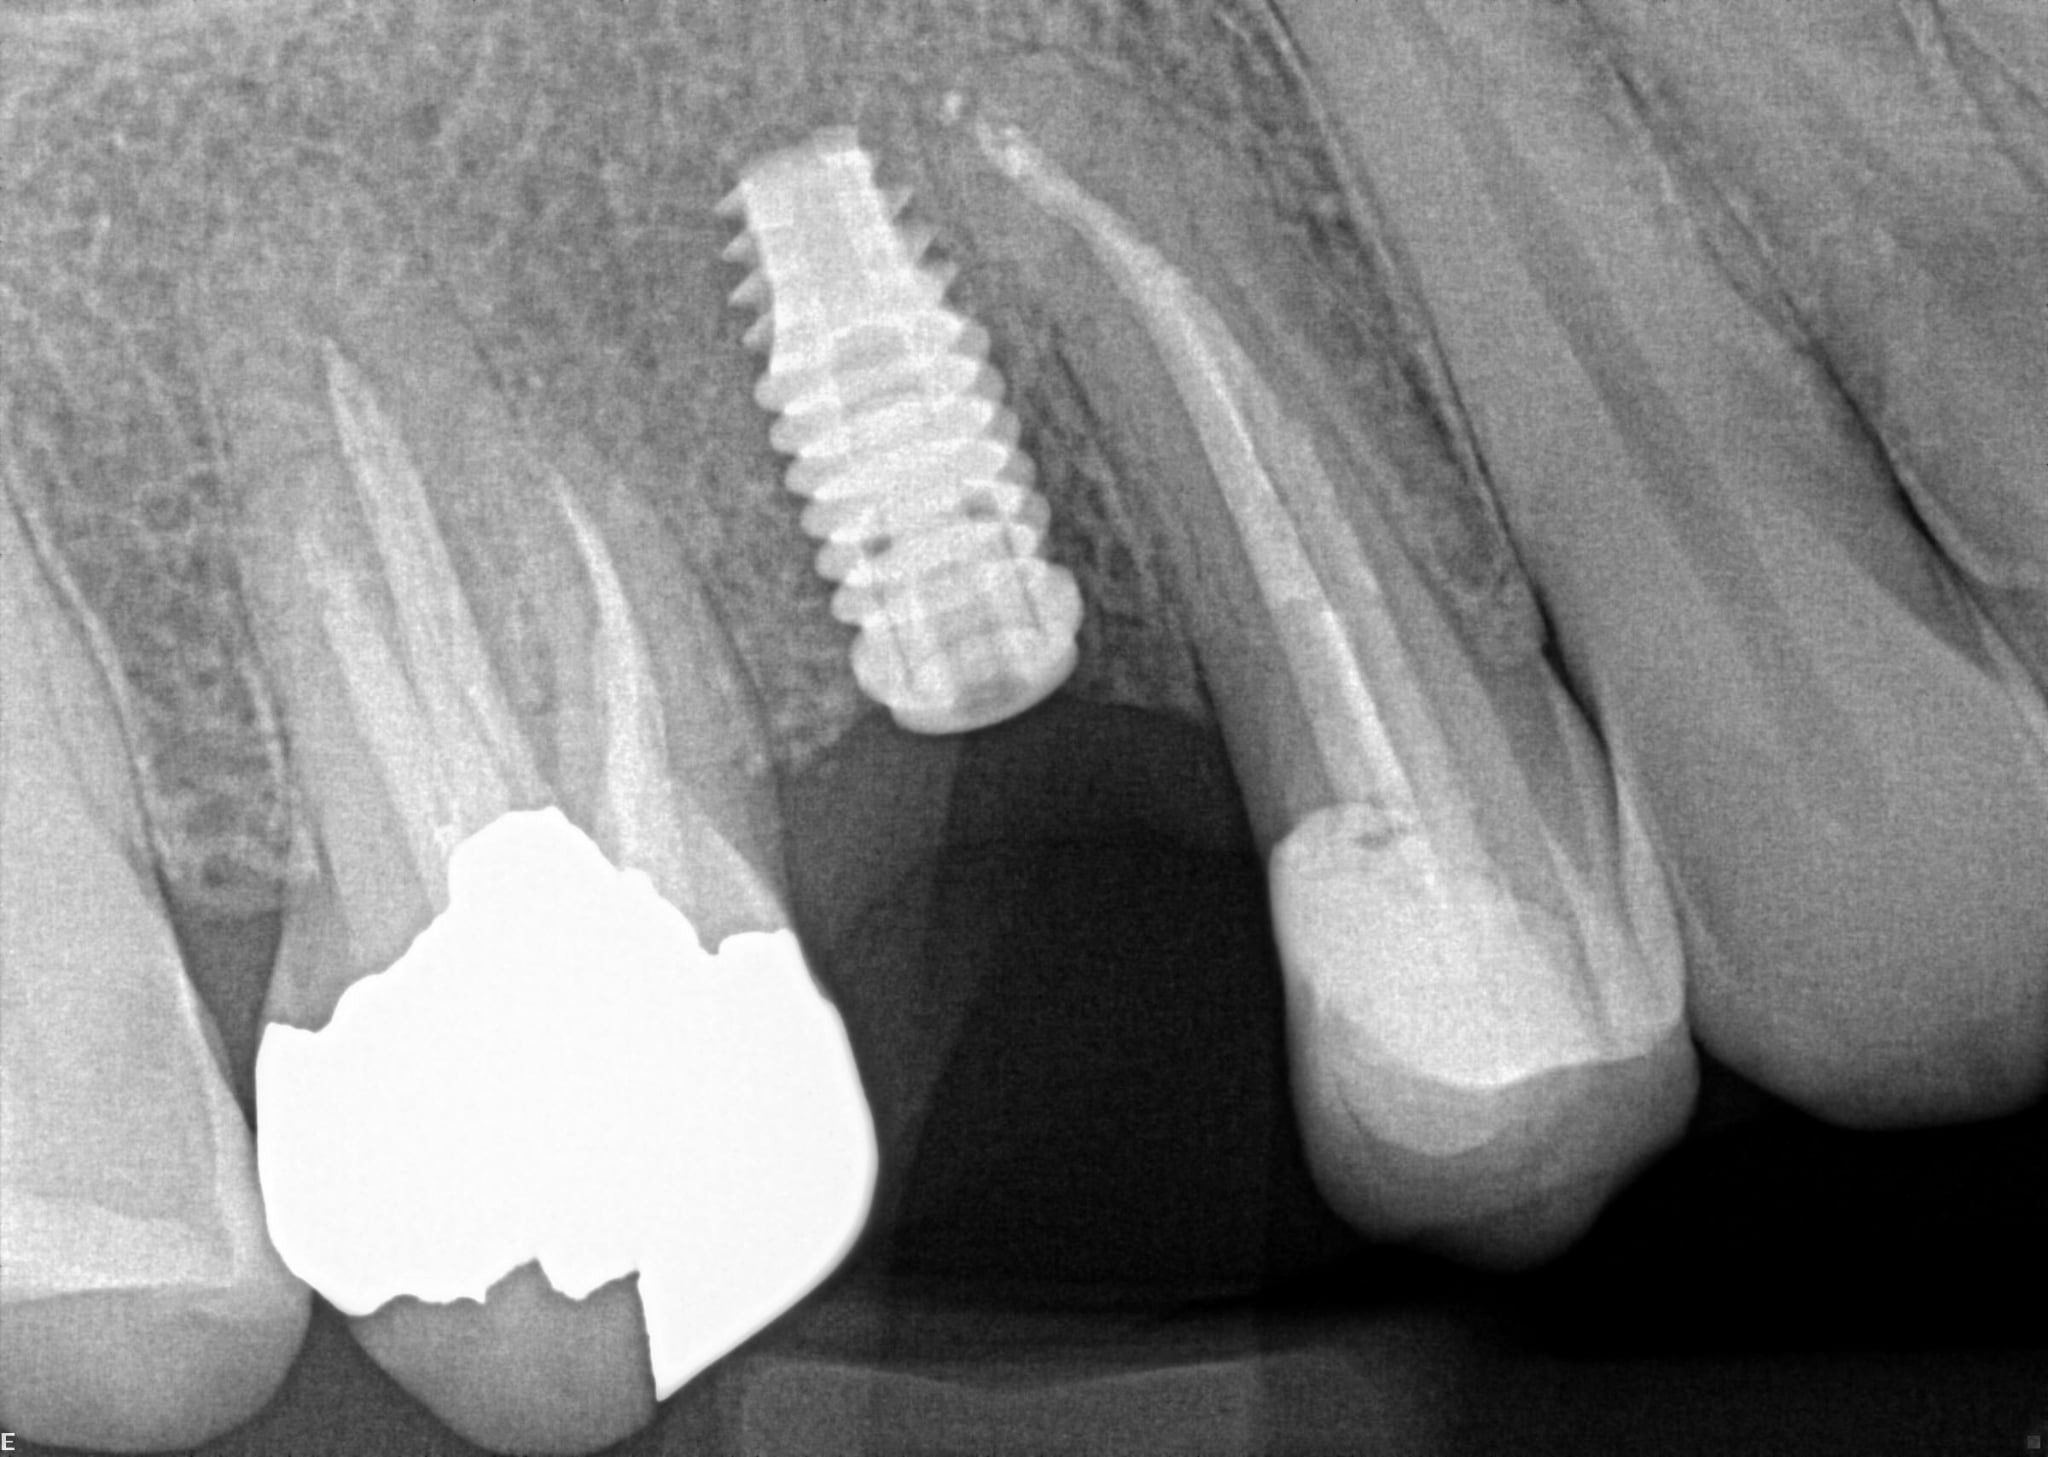

24. On which surface a recurrent caries can be detected?

no recurrent caries can be seen in this X ray